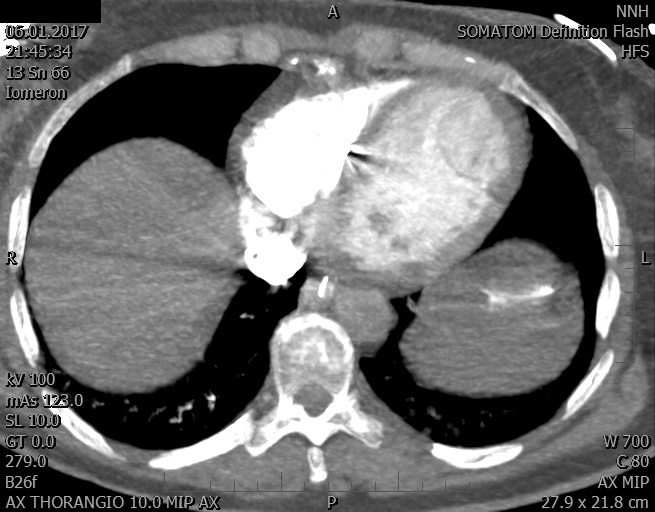

Video 2 - Echokardiograficky byla zjištěna těžká dysfunkce dilatační levé komory s nezvětšenou pravou komorou.Pro nejasnou příčinu zástavy jsme provedli i vyšetření výpočetní tomografií (CT), které vyloučilo plicní embolizaci (série 1 - soubory na konci článku). V den přijetí při přetrvávající oběhové nestabilitě byla nemocná opakovaně defibrilována pro fibrilaci komor se stabilizací rytmu po podání amiodaronu a mesocainu. Dle hemodynamických měření se jednalo o těžký kombinovaný šok. Vstupní laboratorní vyšetření bylo bez větších pozoruhodností. Posléze jsme doplnili anamnézu od příbuzných a zjistili, že pacientka užila do dvou hodin před srdeční zástavou první tabletu amoxicilinu na lehký respirační infekt. Při nevýtěžnosti vstupních vyšetření a nových anamnestických informacích jsme doplnili 14 hodin po kolapsu vyšetření koncentrace tryptázy v séru, která byla extrémně zvýšena (tabulka 2), což nás vedlo k podezření na anafylaxi.